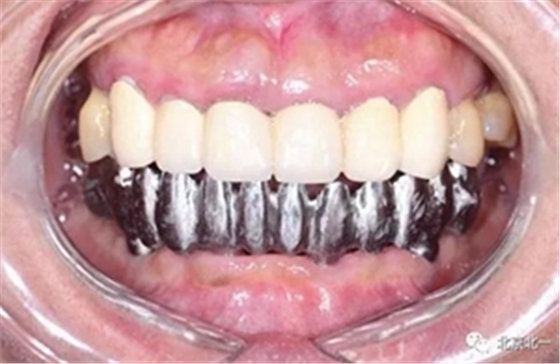

圖十二:臨時即刻當天戴牙, 完成即刻修復(fù)。實現(xiàn)ONE DAY APPLE

圖十三:ONE DAY APPLE

圖十四:口內(nèi)照